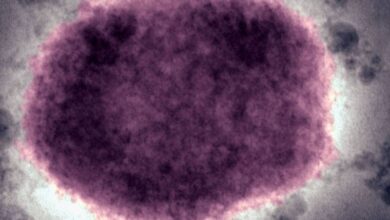

viruela del mono

Emite Ssa aviso epidemiológico por viruela del mono

Viruela del mono: OMS eleva casos a 131, un tercio en España

Apuesta OMS por frenar viruela del mono en países no endémicos

EU reporta primer caso de viruela del mono en Massachusetts